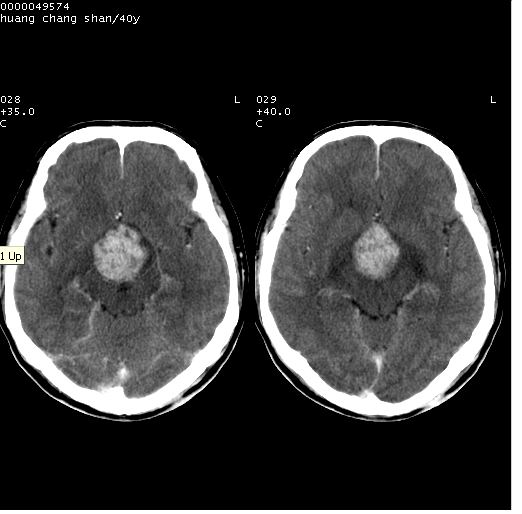

患者 m,40y。头痛,视力模糊,多饮多尿,性欲减退半年余。

行ct平扫+增强,图象如下:

肿瘤强化明显、鞍部骨质结构未见增大、破坏,考虑脑膜瘤可能性大

鞍背无破坏和明显受压,病变明显均匀强化,边界清晰。鞍上区脑膜瘤可能性大,不除外生殖细胞瘤。

平扫病灶呈等密度,增强后强化明显,均匀一致,结合病史首先考虑:垂体瘤。脑膜瘤不支持,因为脑膜瘤平扫多为实性呈均匀高密度影像,内分泌症状多不明显,垂体内分泌素测定正常。

鞍上池肿瘤,鞍背及垂体窝形态变化不明显,病灶强化密度均匀且高度强化,考虑实性颅咽管瘤、生殖细胞瘤及脑膜瘤可能。

结合临床考虑鞍上生殖细胞瘤可能性大于脑膜瘤(增强未见脑膜围征),建议结合冠状位扫描看病灶起源及垂体窝、鞍底情况。垂体窝内未见明显软组织密度影,垂体窝未见扩大,暂不考虑垂体瘤;病灶较大,未见囊变及钙化,颅咽管瘤不支持。期待结果!

1、头痛,视力模糊,多饮多尿,性欲减退半年余,提示:肿瘤为功能性肿瘤。

2、ct表现:肿瘤呈类圆形,均匀略高密度,无囊变,无钙化。侧脑室有扩大。

3、首先考虑:功能性垂体大腺瘤。

4、鉴别诊断:脑膜瘤,瘤体内点状钙化最具特征性,常位于鞍结节。颅咽管瘤,蛋壳样钙化,常有囊变。动脉瘤,位于鞍旁,强化与动脉一致。有时尚需与发生于鞍区的生殖细胞瘤鉴别,生殖细胞瘤钙化亦较常见。

5、友情提示:下回发现鞍区占位性病变,最好加扫冠状位,了解肿瘤与蝶鞍的关系及蝶鞍骨质的改变。